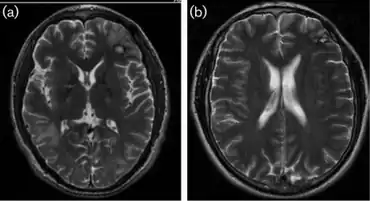

| a)MRI- oedema from mass in right temporal b) MRI- two years afterword conclusion of the CNS lesions | |